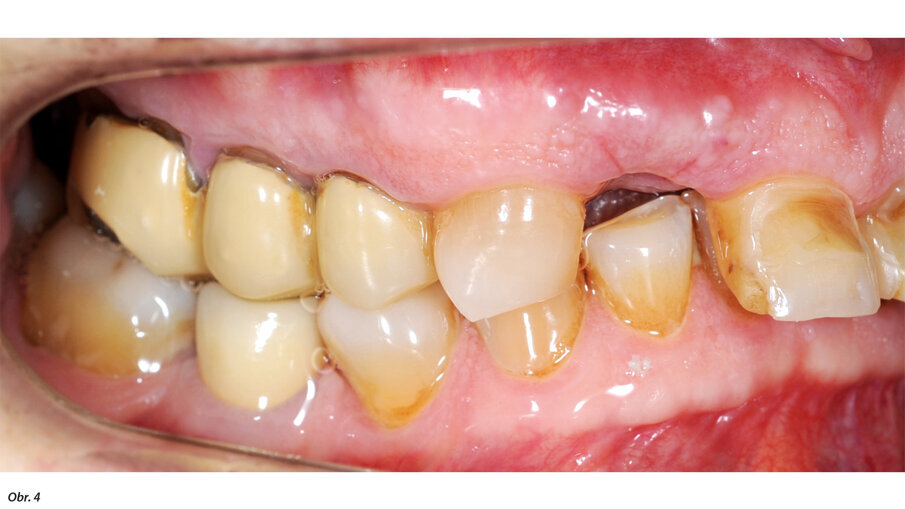

66letý pacient s non-inzulin dependentním diabetes mellitus a ischemickou chorobou srdeční se dostavil na ošetření parodontálního abscesu v oblasti radix relicta 12 a vícečetných fraktur stávajících náhrad (obr. 1–6). Během návštěvy byla zjištěna značná malokluze a ztráta VRO, abraze a fraktury stávajících náhrad i zbylých zubů a známky cervikální abfrakce. Pacient také trpěl mírnou bolestivostí svalů při palpaci, a to zejména v oblasti m. pterygoideus medialis et lateralis, sníženou schopností otevírání úst a slabými zvukovými fenomény v oblasti temporomandibulárních kloubů.